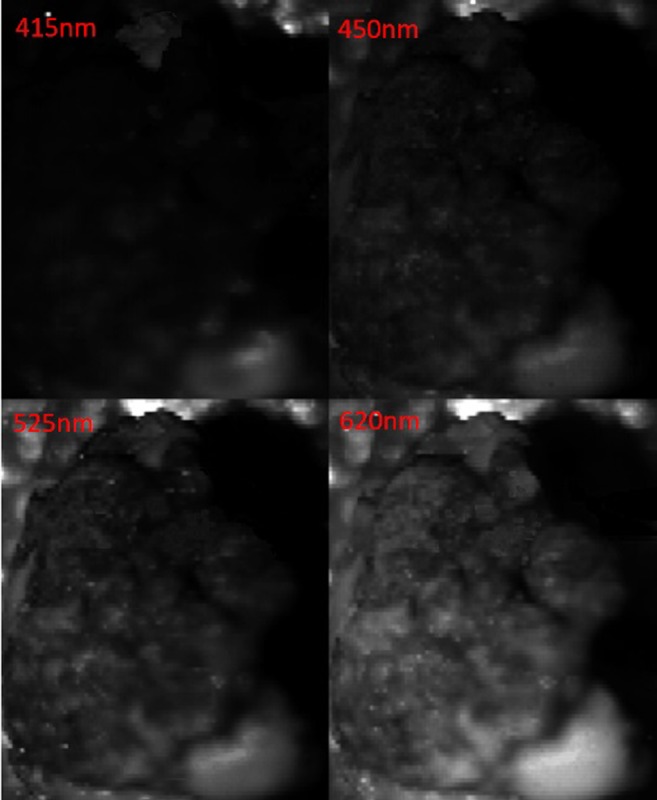

The sample tissue was placed on the workbench below the miniature snapshot NBI system (Fig. 4). Under the illumination of a white light source which was available in a surgical operating room or in a typical office, the snapshot NBI system captured, with every single exposure, a single raw image of the cervical cancerous tissue. However, from everyone raw image, four spectral images centered at wavelengths of 415, 450, 525, and 620 nm were instantly split and displayed side-by-side (Fig. 6).

Fig. 6.

The simultaneously collected four characteristic narrow-band spectral images centered at 415 nm, 450 nm, 525 nm, and 620 nm of the sample, captured at a single exposure